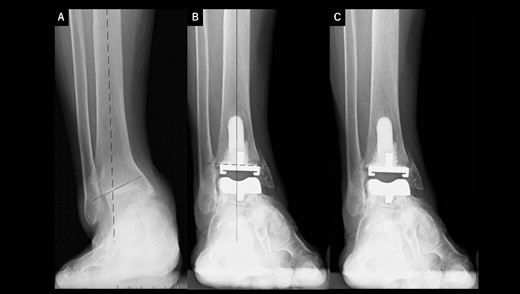

A 72-year-old man with end-stage ankle OA and severe ankle joint pain and gait dysfunction had a JSSF ankle/hindfoot scale score of 42 points. Talar tilt was 11° varus (Fig. 1A). He underwent TAA with medial malleolar osteotomy without internal fixation, and the tibial component was placed in the 5° varus position (Fig. 1B). Within 6 months, the tibial component showed varus migration, and nonunion at the medial malleolar osteotomy occurred (Fig. 1C). Revision TAA with mini-plate fixation at the medial malleolus was then performed (Fig. 1D), but the tibial component was still placed in the varus position (3° varus); subsequently, varus migration of the tibial component occurred again (Fig. 1E). After that, vitamin D administration and low intensity pulsed ultrasound treatment were continued for more than 1 year, and bone union was achieved, but both the tibial and talar components showed malposition (Fig. 1F). At present, four years after revision TAA, he can walk for more than 1.5 hours and play golf.

Radiographs of preoperative weight-bearing radiograph of the antero-posterior ankle joint in Case 1. (A) Preoperative. Talar tilt is 11° varus. Opening of the lateral gutter with os subfibulare is seen. (B) One month after surgery. Medial malleolar osteotomy without internal fixation, and tibial component placed in the 5° varus position. Opening of the lateral gutter still remains. (C) Five months after surgery. The tibial component shows varus migration, and nonunion at the medial malleolar osteotomy has occurred. Opening of the lateral gutter is exacerbated. (D) One month after revision surgery. The site of the medial malleolar osteotomy is fixed with a mini-plate, and varus positioning of the tibial component still remains (3° varus). The lateral gutter is closed. (E) Three months after revision surgery. Varus migration of the tibial component has occurred again, and bone union at the osteotomy is still not seen. (F) Four years after revision surgery. Bone union has been achieved, but both tibial and talar components show malposition. The lateral gutter is still closed.